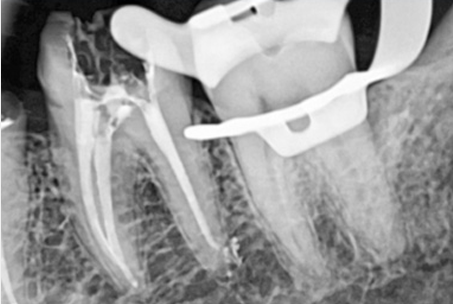

The images above show actual cases treated at SMILE FACE DENTAL CLINIC.

To a non-specialist, they may appear to be ordinary X-rays, but dentists can instantly recognize them.

They can appreciate both the complexity of the treatment and the care and precision involved.